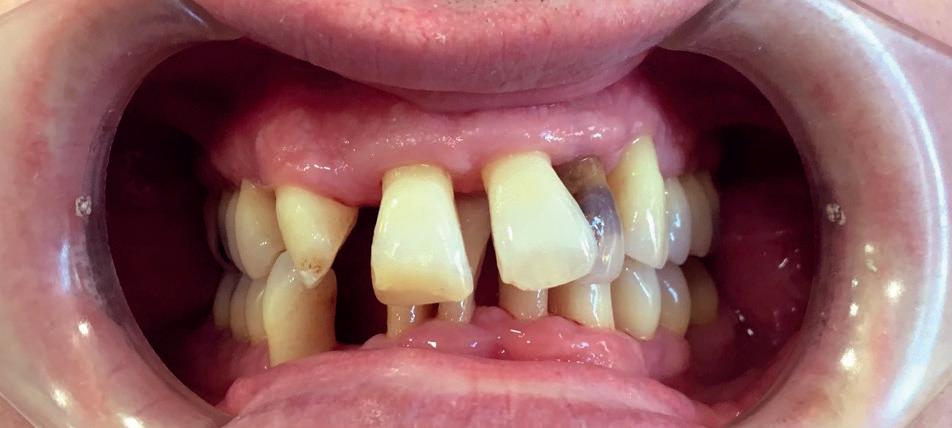

Where the Australian public healthcare system REALLY seems to fall down though is, yes, you guessed it: dentistry.

Adult dental patients are pretty much abandoned as far as Medicare is concerned, with dental care being largely excluded from standard Public Healthcare System benefits. This means that most adult patients typically have to pay out-ofpocket or use private health insurance that includes dental cover.

For low-income earners and some eligible groups, they MAY be able to access subsidised or free dental care through public dental clinics although access can vary from state to state. Waiting times can be long.

For children, care is governed by the Children’s Dental Benefits Schedule (CDBS). Medicare covers eligible children between the ages of two to 17 for up to $1,095 over two years for basic dental services. This is roughly £550. Though including exams, X-rays, cleaning, fillings, and extractions, families must receive certain meanstested ‘Centrelink’ Family Tax Benefit payments to qualify, and not every family with children automatically receives this benefit.

The public health Medicare system MAY cover dental surgery performed in a public hospital – especially if it’s deemed to be medically necessary - examples being severe infection, injury, or oral surgery related to other conditions.

The Aussies I spoke to about their dental health system seemed to be at ease with the situation, adopting a laissez-fair, ‘no worries’ attitude to their dental access. It was obviously only my wife and I that were mildly alarmed at the apparent inadequacies in terms of access to public health dentistry for your ‘standard’ adult and child, though that’s probably because I had an NHS contract from qualification to retirement, while my wife had to listen to me whingeing on about it for nigh on 30 years.

To me (from the outside and now over 10,000 miles away), it looks like teeth have been as good as abandoned by the Australian public health service and my fear is that we are only a brief stopover in Dubai before reaching that point ourselves. Since the Aussies lived under mostly privately funded healthcare before the 1970s,

with Medicare only being introduced in 1984, they seem to be used to the idea that teeth can pretty much fend for themselves. But should they?

Aneurin Bevan had a clear and overriding philosophy behind his setting up of the National Health Service: healthcare should be a right, not a privilege. And surely, overall healthcare MUST include dentistry?

Organisations like Toothless In England and the British Dental Association, and thousands of dental professionals, and millions of UK citizens accept that dentistry is healthcare, but the people in Government still haven’t grasped the concept of what constitutes a crisis. And strewth, is this a crisis, or what? Well, the UK’s Public Accounts Committee (PAC) certainly thinks so having said that the national dental plan set out by the former Tory Government had “comprehensively failed.”

It certainly feels like dentistry and patients have been abandoned when a Freedom of Information request by the Liberal Democratic Party revealed that there were 16,100 A&E attendances related to tooth decay in 2024, and nearly 3,000 of those patients were children.